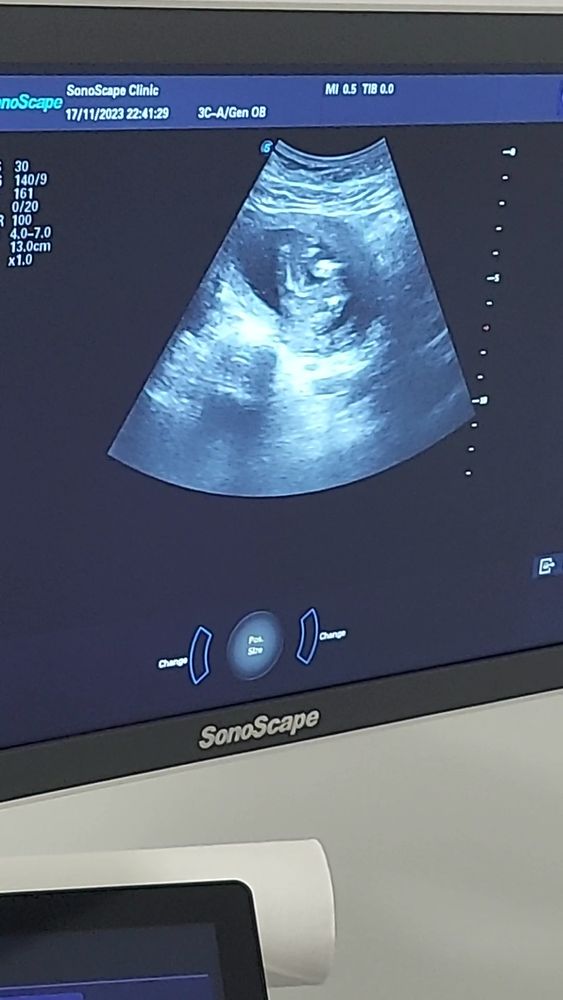

Сегодня узнаем кто в домике живет) (много фото узи) а вы как думаете?)

Девочка 100% подтверждено на 22 неделе.

Плохое качество фото, видно что все они сняты между ног, но не чётко, вообще яичек нет вроде бы, значит девочка.

УЗИ 12 недель Точно девочка?)